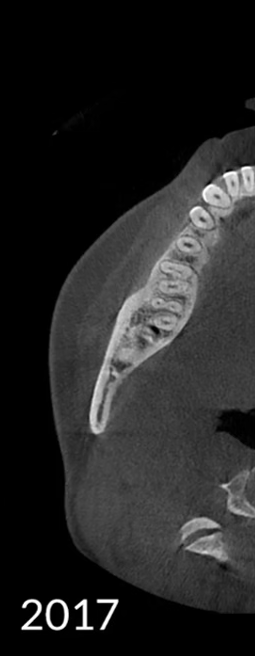

Các hiện vật kim loại được xóa bằng công nghệ AI và cấu trúc răng, mão kim loại và cấy ghép được phục hồi chính xác dựa trên các nguyên tắc toán học.

Không có MAR

MAR cũ

MAR mới